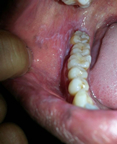

口腔扁平苔藓是一种常见的慢性口腔黏膜皮肤疾病,一般不具有传染性。该病的发病机制尚未完全明确,目前的研究表明,其发病与精神因素...... [详情]

多数人对口腔溃疡比较熟悉,但对于大部分人来说扁平苔藓可能还是个陌生的病称。扁平苔癣是什么病?口腔里长扁平苔藓依据病损形态和严重程度的不同,可分为不同类型,要想战胜它,就先要了解它... [详情]